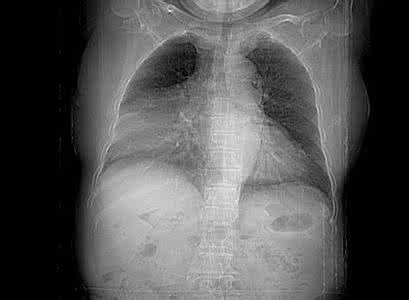

胸部X线检查在心膈角处有明显阴影,深呼吸和体位改变可见阴影形态和大小都有明显改变。

1.X线表现

①囊肿常发生在心隔角区右侧多见。

②囊肿呈圆形或椭圆形密度均匀边缘清楚。

③侧位上囊肿靠前贴近前胸壁。

④透视下胸腔压力变化可致变形。